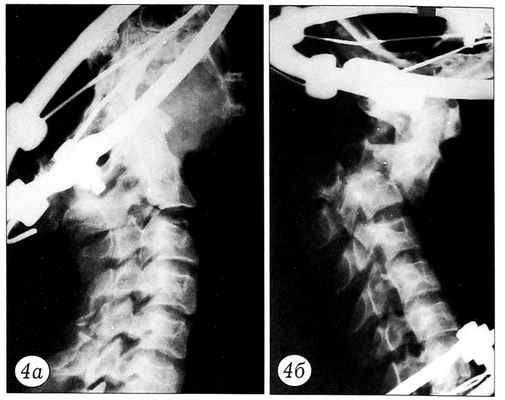

Результаты нагрузочного теста документировались графически. По оси ординат регистрировалось усилие в ньютонах, по оси абцисс — степень смещения позвонков в миллиметрах (рис. 2). При этом основное внимание уделялось величине нагрузки, при которой происходило наибольшее смещение позвонков. До и после нагрузочного теста производилась рентгенография блоков (рис. 3~5).

Рис. 4. Перелом «палача» типичный до (а) и после (б) нагрузочного теста.

Рис. 5. Перелом Джефферсона до (а) и после (б) нагрузочного теста. На рентгенограмме в боковой проекции после нагрузки видно расширение щели сустава Крювелье.